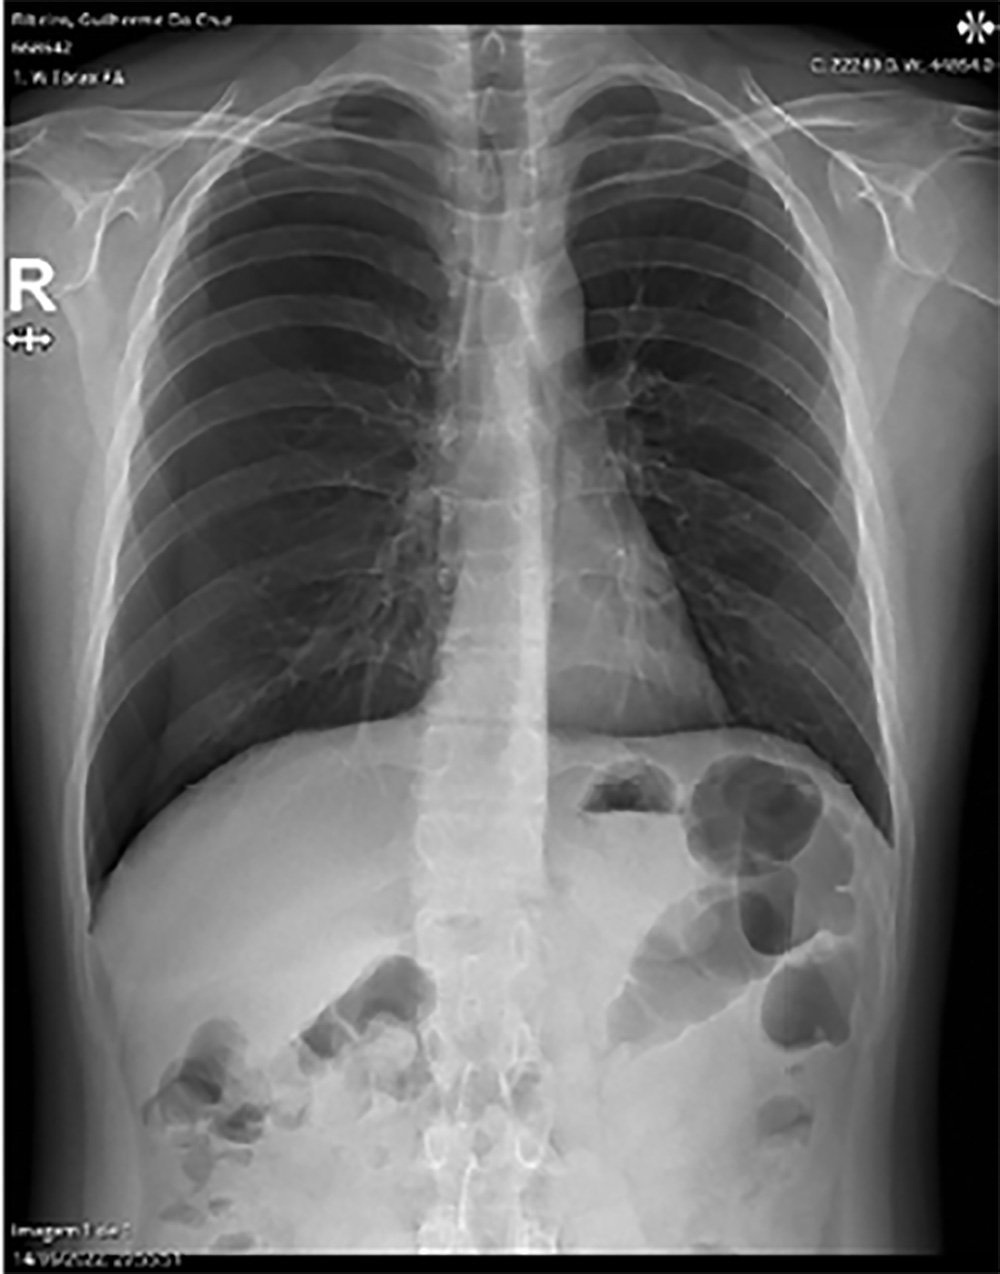

A radiografia mostrou a existência de um pneumotórax de grandes dimensões segundo a British Thoracic Society (BTS >2 cm) com colapso moderado (entre 15% e 60% do pulmão) no campo pulmonar direito, provavelmente como consequência da perfuração pleural pela agulha da acupuntura (Fig. 1).

Figura 1: Radiografia de tórax póstero-anterior (PA) à entrada (pneumotórax de grande dimensão à direita).